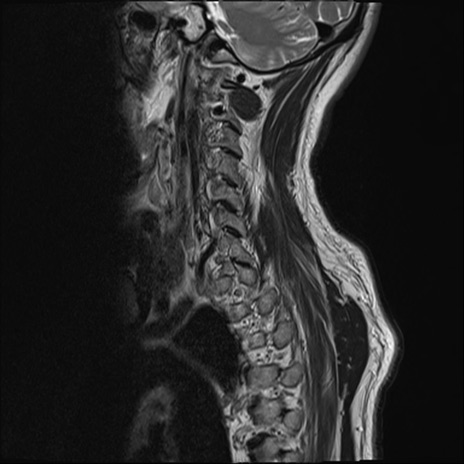

【整形】TIPS症例7 頚椎MRI T2WI(矢状断像)

頚椎MRI

矢状断像と横断像